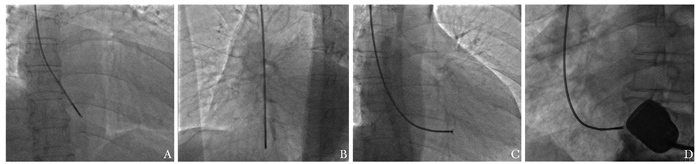

• 摘要: 经皮心内膜心肌活检是利用心肌活检钳经外周血管夹取心内膜心肌组织的技术,迄今在临床上应用已超过50年,且相关技术不断更新。目前心内膜心肌活检及心肌病理学诊断已成为诊断心肌炎、心肌病的重要手段。北京协和医院心内科已进行500余例心内膜心肌活检操作,积累了一定的经验,因此特制定经皮心内膜心肌活检临床操作规范,主要包括其适应证、禁忌证、操作要点、标本处理及术后监测等,并提出了并发症的处理策略。由于经皮心内膜心肌活检具有漏检的可能,需与超声心动图、心脏MRI及心血管病理学等方面专业医师密切配合,以减少漏诊、误诊。建议全国心内科医师高度重视并积极开展此项检查,以提高我国心肌炎、心肌病的精准诊断能力。

Abstract: Percutaneous endomyocardial biopsy (EMB) is a technique that biopsy samples are obtained using the bioptome through a peripheral blood vessel. The technique has been used and refined for more than 50 years in clinical application. Now EMB has become an important tool of the diagnosis of myocarditis and cardiomyopathy. The department of cardiology of Peking Union Medical College Hospital (PUMCH) has performed more than 500 cases of EMB and accumulated abundant practical experience. The clinical practice guideline of percutaneous EMB was also established in PUMCH, including indications, contradictions, key points of the operation, sample handling and processing, post-procedure monitoring, and the treatment strategy for potential complications, etc. Due to the limitation of EMB, cardiologists should collaborate with experts on echocardiography, cardiac magnetic resonance and cardiac pathology to decrease the probability of missed diagnosis and misdiagnosis. Cardiologists should pay much attention to the value of EMB and actively perform EMB to improve the diagnosis level of myocarditis and cardiomyopathy in China.